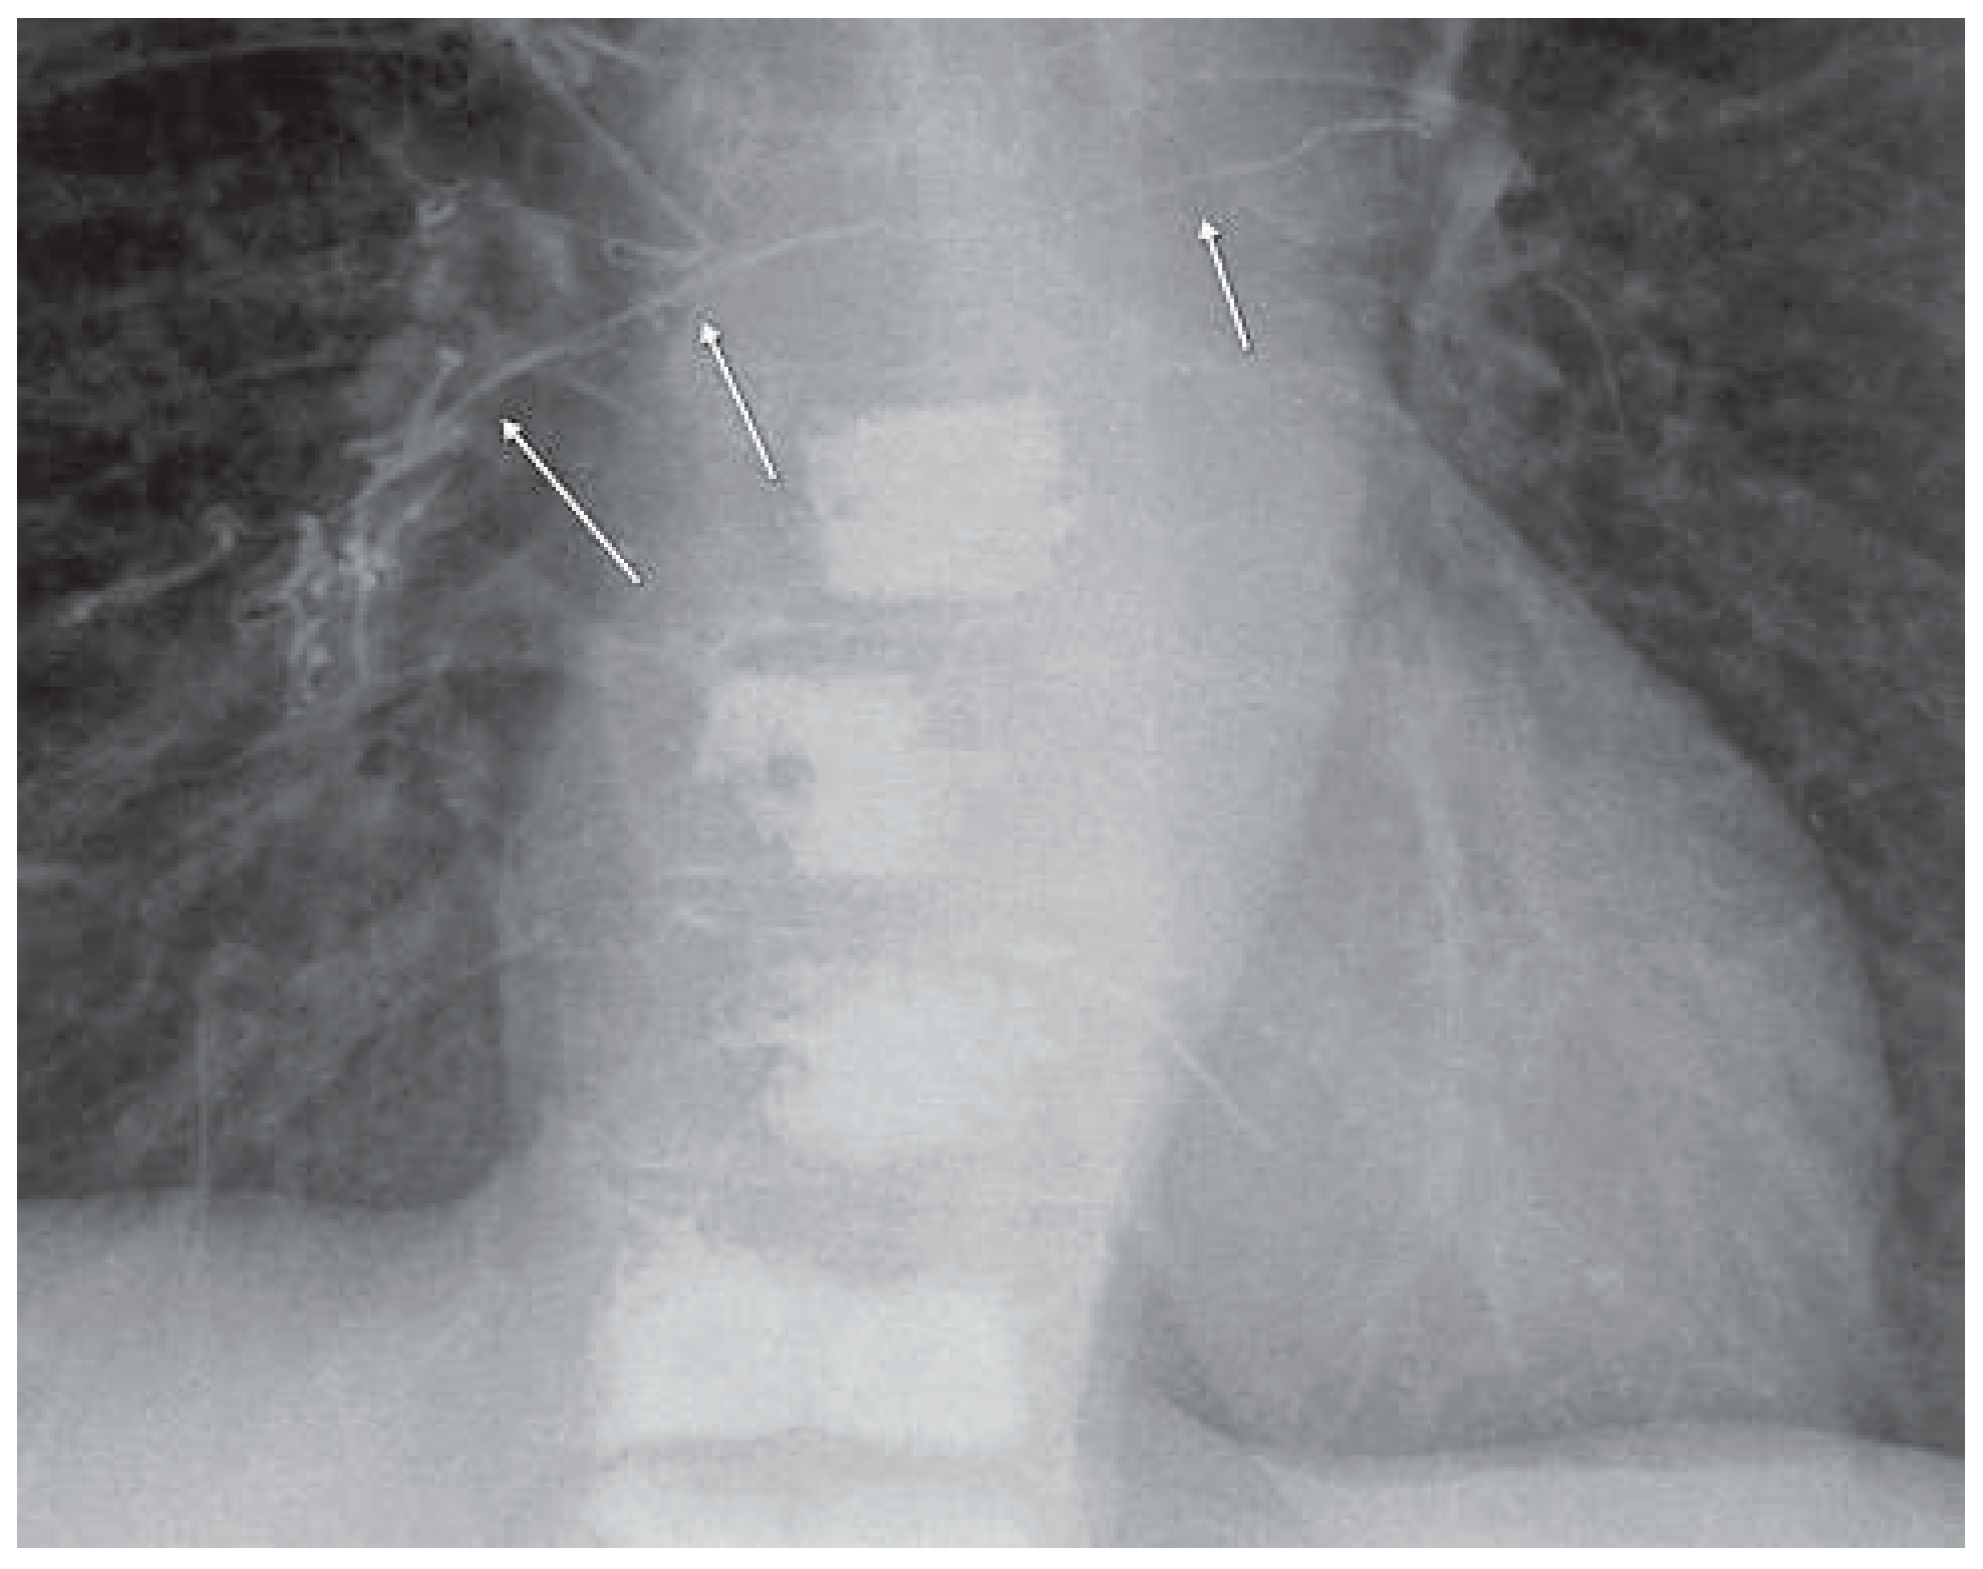

Acrylcement Pulmonary Embolism

Zumsteina, D.; Widmer, F.; Blay, M. Acrylcement Pulmonary Embolism. Cardiovasc. Med. 2013, 16, 95. https://doi.org/10.4414/cvm.2013.00118